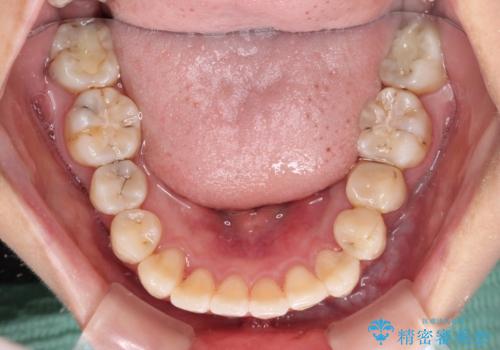

歯磨きしやすくなるとともに、飛び出していた前歯も引っ込めて整えることができました。